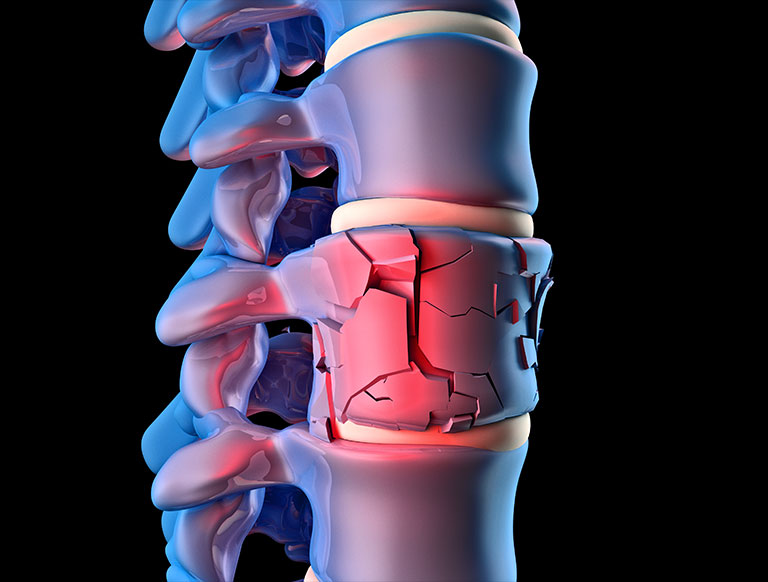

Osteoporotic spine fractures, also known as vertebral compression fractures (VCFs), occur when the vertebrae become so weak that even minor stresses, such as bending, lifting, or coughing, can cause them to collapse. The primary cause of these fractures is the loss of bone density associated with osteoporosis. Several factors contribute to osteoporosis, including:

Osteoporotic spine fractures can lead to a range of symptoms and complications. Acute fractures often cause sudden, severe back pain that may be accompanied by limited mobility and tenderness over the affected vertebra. In some cases, pain may radiate to the abdomen or flank. Chronic fractures can result in spinal deformities, such as kyphosis (a forward curvature of the spine), which can lead to a stooped posture.

In cases where conservative treatment is insufficient, minimally invasive surgical procedures such as vertebroplasty or kyphoplasty may be considered. These procedures involve injecting bone cement into the fractured vertebra to stabilize it and alleviate pain.